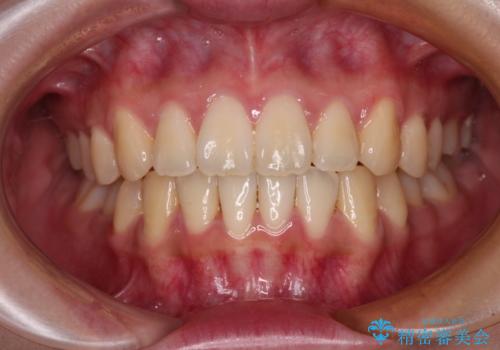

しっかりと装着時間を守ってくださったので、予定通り1年強で治療を終えることができました。

- 前歯の捻れを気にして来院された患者様です。

上顎前歯が捻れて前方に飛び出しており、下顎前歯もそれに沿うようにデコボコとなっていました。

IPR(歯と歯の間を削る処置)によりスペースを獲得して下顎前歯のデコボコを改善し、上顎前歯は下顎前歯と接する位置にまで引っ込めるように設定し、インビザラインにて矯正治療を行うこととしました。